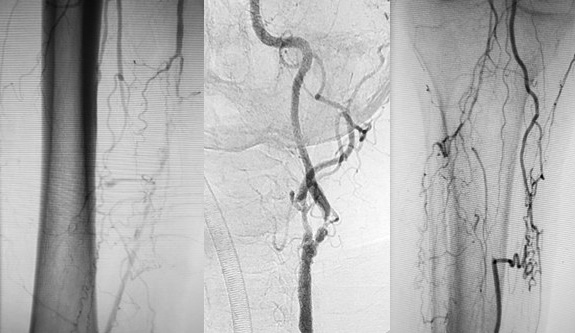

Artérias são os vasos responsáveis por levar o sangue do coração para cada órgão e tecido de nosso corpo, exercendo função de irrigação e nutrição aos órgãos e tecidos…

Aneurismas Arteriais

caracterizados pela dilatação de uma ou mais artérias, excedendo em 50% o diâmetro normal do vaso. Dentre as suas principais causas encontram-se o tabagismo….